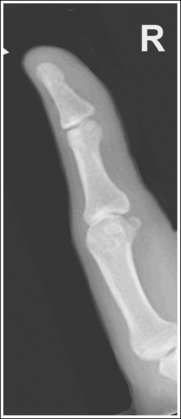

Lateral Finger Projection Analysis

See Figure 4-10 and Box 4-4.

The digit of interest is in a lateral projection. The anterior aspect of the middle and proximal phalanges demonstrates midshaft concavity, and the posterior aspects of the phalanges show slight convexity.

• A lateral finger projection is accomplished by rotating the affected finger 90 degrees from the PA projection (Figure 4-11). Whether the hand is rotated internally or externally to obtain this goal depends on which direction will bring the finger closer to the IR. Typically, when the second and third fingers are imaged, the hand is rotated internally and, when the fourth and fifth fingers are imaged, the hand is rotated externally.

• Distinguishing lateral projection from rotated projection. To understand the difference between a truly lateral digit projection and a lateral projection that is rotated, study a finger skeleton in lateral and PA and AP oblique projections. Note how the midshaft concavity of the middle and proximal phalanges varies as the digit is rotated. In a lateral projection, the anterior aspect of these phalanges is concave, but the posterior aspect demonstrates slight convexity. In PA and AP oblique projections, both sides of the middle and proximal phalangeal midshafts demonstrate concavity, but the side toward which the anterior surface is rotated demonstrates a greater degree of concavity than the side toward which the posterior surface is rotated. The soft tissue width at either side of the phalanx also changes in the lateral and PA and AP oblique projections. More soft tissue is present on the side of the phalanges toward which the anterior surface is rotated (see Image 7).